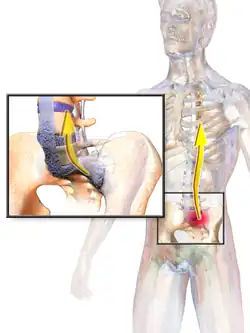

AS can occur in any part of the spine or the entire spine, often with pain localized to either buttock or the back of the thigh from the sacroiliac joint. Arthritis in the hips and shoulders may also occur. When the condition presents before the age of 18, AS is more likely to cause pain and swelling of large lower limb joints, such as the knees.[14] In prepubescent cases, pain and swelling may also manifest in the ankles and feet where heel pain and enthesopathy commonly develop.[14] Less common occurrences include ectasia of the sacral nerve root sheaths.[15]

Surgery

Prognosis is related to disease severity.[12] AS can range from mild to progressively debilitating and from medically controlled to refractory. Some cases may have times of active inflammation followed by times of remission resulting in minimal disability while others never have times of remission and have acute inflammation and pain, leading to significant disability.[12] As the disease progresses, it can cause the vertebrae and the lumbosacral joint to ossify, resulting in the fusion of the spine.[45] This places the spine in a vulnerable state because it becomes one bone, which causes it to lose its range of motion as well as putting it at risk for spinal fractures. This not only limits mobility but reduces the affected person's quality of life. Complete fusion of the spine can lead to a reduced range of motion and increased pain, as well as total joint destruction which could necessitate a joint replacement.[46]